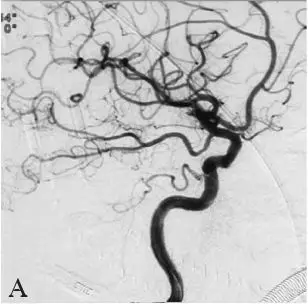

B:右侧颈内动脉造影;

DSA:急诊全脑血管造影提示右侧颈内动脉发出变异的原始三叉动脉,该三叉动脉直接向右侧小脑前下动脉(AICA)供血区域供血,在原始三叉动脉自颈内动脉发出部位可见1枚梭形动脉瘤(图18-1B、C),右侧椎动脉发育较差,仅供血小脑后下动脉(PICA)区域(图18-1D)。右侧小脑前下动脉(AICA)未见显影,可见基底动脉发出的部分回旋支显影(图18-1E)。其余血管造影未见明显异常。

DSA:急诊行全脑血管造影提示基底动脉下段可见1枚形态不规则囊性动脉瘤(图18-3B)。三维重建后提示基底动脉下段开窗畸形,动脉瘤瘤颈位于开窗近段分叉处,瘤顶有子囊(图18-3C),动脉瘤瘤颈1.85 mm,瘤深5.45 mm,瘤宽2.77 mm。左侧椎动脉造影提示左侧椎动脉仅供血小脑后下动脉(PICA)区域,未汇入基底动脉(图18-3D)。颈内动脉造影未见明显异常。

B:右侧椎动脉造影示基底动脉下段可见1枚形态不规则囊性动脉瘤;